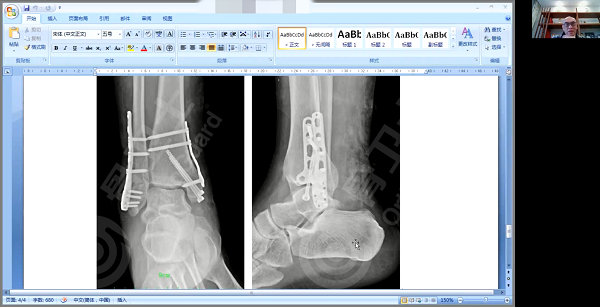

病例二是一位右内外踝骨骨折患者,男,45岁,因摔伤导致右踝内外踝关节内骨折。入院第三天,医院对患者进行解剖复位手术治疗,外踝采用接骨棒螺钉固定,内踝用空心拉力钉+钢板固定。

杨述华教授肯定了该患者治疗方案,他强调,踝关节内骨折治疗标准不存在功能复位,一定要达到解剖复位的标准。从影像资料看,该患者手术非常成功,适应征、手术方式选择得非常好,既达到了解剖复位,又促进了骨折愈合。由于该患者伴有软组织、肌腱损伤的情况,杨述华教授建议在手术后要用支具或石膏固定1-1.5个月。